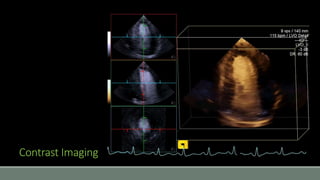

Contrast Imaging

• #42 The problem with 3D, even more than 2D, is to obtain a good delimitation of chambers for surface rendering. The natural complement to 3D is the use of echo contrast. Contrast is quite widely used in the US. It consist of micro-bubbles, encapsulated in various types of shells. Because of the impedance difference, air is a strong US reflecting medium, and produces very bright echos.

• #43 And here, when used with a 3D echo machine. Chamber tracing becomes quite easier.